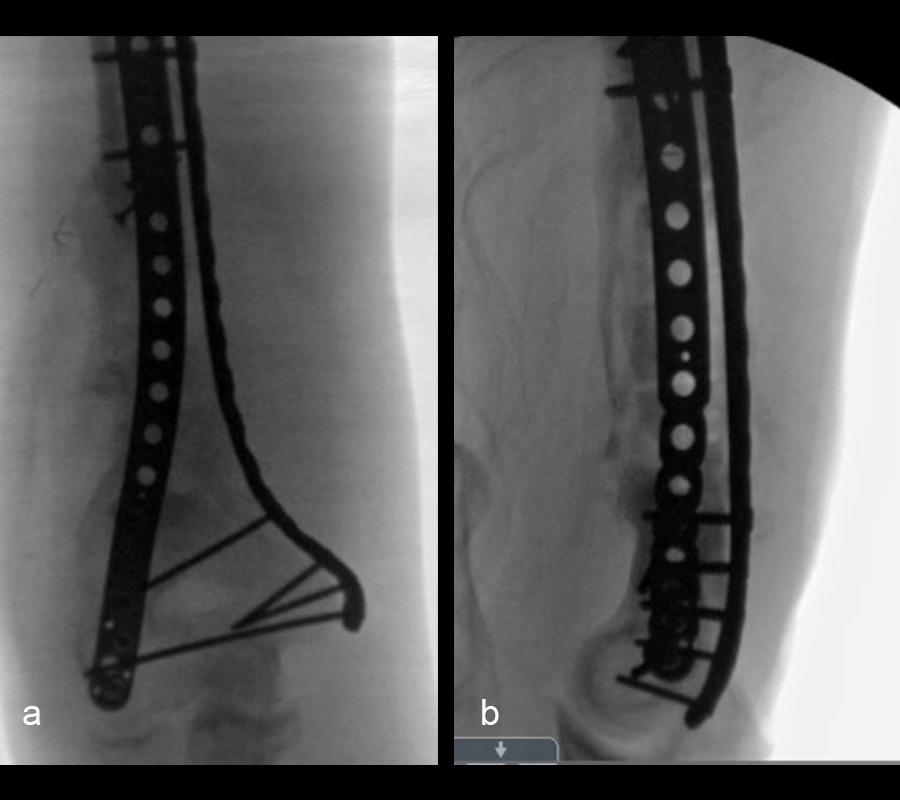

In a first stage, the distal humerus was debrided and devitalized bone was resected, leaving an 8cm defect into which a cement spacer was placed. New plates were inserted to stabilize the fracture (Fig 17 and Fig 18). Cultures taken in the OR were negative.